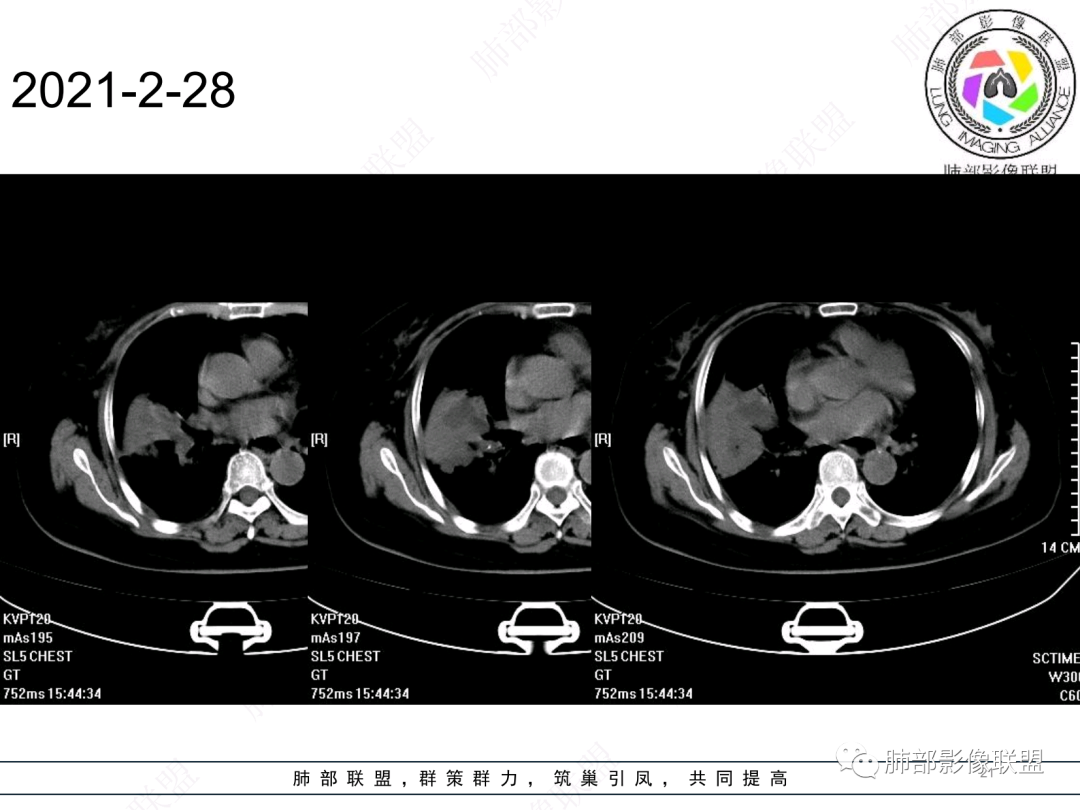

慢性咳嗽,抗炎复查无好转,原右肺中叶实边,外侧段支气管开口阻断,复查无好转,逐渐向下叶外前基底段融合形成大肿块,边缘膨隆,密度不均匀,坏死轮廓不清,内血管束破坏,累及中轴间质厚,外围分布,方向恶性,与炎性肉芽肿鉴别,隐球荚膜抗原先排查!

女,74岁,咳嗽咳痰加重一周入院,右肺中叶大片实变影,边界清晰,病灶内密度不均匀,右肺中叶支气管变窄,增强扫描病灶明显强化,考虑恶性病变能,鉴别肺脓肿。

右肺中叶实变,支气管开口阻断,边缘膨隆,密度不均匀,坏死边界清晰,胸膜累及,。一般抗感染治疗无效。考虑恶性。

老年女性患者,慢性病程,两次活检均提示炎性病变,胸部CT:右肺中叶大片实变密度影,边界尚清楚,部分收缩,部分膨隆,内部有低密度坏死,坏死边界清楚,无明显结节感,无分割,总体考虑炎性病变,机化性肺炎,NTM,慢性肺脓肿,鉴别:恶性,腺癌

右肺中叶大片实变,内见大片的坏死,中叶外侧段支气管阻塞,相邻胸膜增厚,间隔约四个月后复查,发现低密度坏死内可见气泡影,老年人,反复迁延不愈的病变要考虑恶性,首先考虑腺癌伴感染。鉴别慢性脓肿。

右肺胸膜下实变,跨叶,形态不规则,局部边缘膨隆,中叶支气管外侧段进入后阻塞伴不张,不均匀强化,其内坏死边界欠清晰,复查无吸收,考虑腺癌,鉴别慢性炎症伴脓肿

右肺大片状高密度灶,跨叶,密度不均,边缘膨隆,支气管阻塞,粘液栓,不均匀强化,其内坏死边界欠清晰,复查无吸收,考虑腺癌,鉴别慢性炎症,脓肿

胸部CT:右肺中下叶大片实变影,界清,边缘膨隆为主,中叶外侧段支气管截断。增强不均匀强化,边缘可见血管影迂曲模糊,内见条带状低密度影。治疗后病变进展。考虑恶性,鳞Ca?鉴别TB、OP。

老年女性,慢性病史,炎性指标稍高,肿标正常,右中下肺大片实变,跨叶生长,边界清,收缩力差,膨隆生长为主,支气管杵状截断,均匀强化,其内坏死边界清,可见悬浮气泡,整体观察,病灶膨隆生长为主,邻近肺野无播散灶,形态单一,尽管慢性病史,影像不支持OP和TB,支气管截断呈杵状,肿标正常,均匀强化,虽是高龄患者,诊断恶性肿瘤有点牵强,综和分析,首选炎性病变放线菌感染,其次考虑低度恶性占位炎机母。